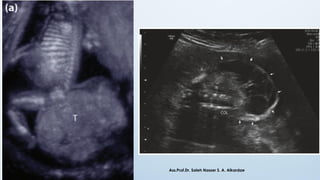

* Sometime the primitive streak persists and result in congenital

anomalies called as Sacrococcygeal Teratoma

Sacrococcygeal Teratoma

❖ Prevalence: 1 in 35,000

❖ Gender: Female (80%) affected more as

compare male.

❖ Morphology: Sacrococcygeal teratoma

consists of cells which are derived from

pluripotent primitive streak cells.

❖ These tumors contains tissues derived all

three germ layers in incomplete stage of

differentiation

❖ Can be diagnosed antenatally with of

Ultrasonography. Ass.Prof.Dr. Saleh Nasser S. A. Alkardae